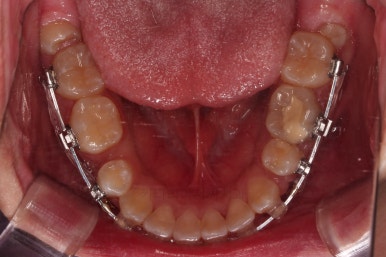

순차적으로 장치를 붙여가며 치아를 가지런하게 합니다.

가지런하게 하는 단계를 거친 뒤,당기기 과정에 들어가는데요.

이 과정에서 입이 들어가는 양, 중앙선, 기울기, 앞니 각도 등등 많은 것을 신경써서 당기기를 해주는데요.

이 때 필요한 것이 미니스크류 입니다.

예전과는 다르게 미니스크류를 이용해서 좀 더 정교하고 고난이도의 치료가 가능해지게 된거죠.

다양한 위치/방향/방법으로 치열을 개선해 나갑니다.